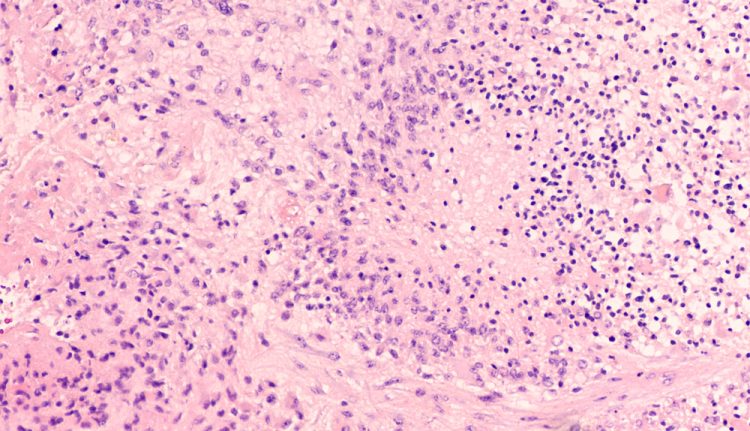

A study has identified more than 200 genes that drive the progression of glioblastoma and which the researchers say present drug targets.